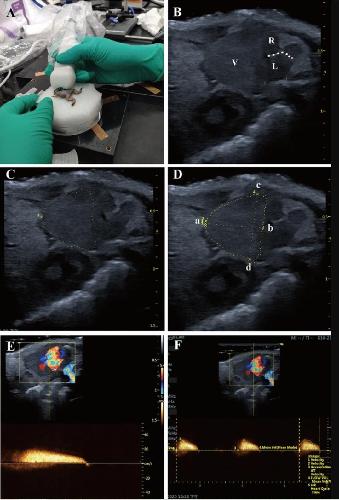

Fig. 1 The morphology and anatomy of the X. tropicalis heart can be observed clearly using small animal echocardiography A: The cardiac images are obtained from the parasternal long-axis of X. tropicalis using small animal echocardiography. B: Representative image of the subcostal 3-chamber view of the X. tropicalis heart under B-mode echocardiography. Ventricle (V). Right atrium (R). Left atrium (L). Atrial septum (dashed line). C: Diagram showing the diastole end ventricular girth (dashed line). D: Diagram showing the diastole end ventricular length (a to b) and diastole end ventricular width (c to d). E: Representative image of pulsed-wave Doppler of the ventricle for hemodynamic analysis. Assessed area (dotted rectangle). F: Measurement of peak blood flow velocity and blood flow acceleration of the ventricle. Assessed area (dotted rectangle)